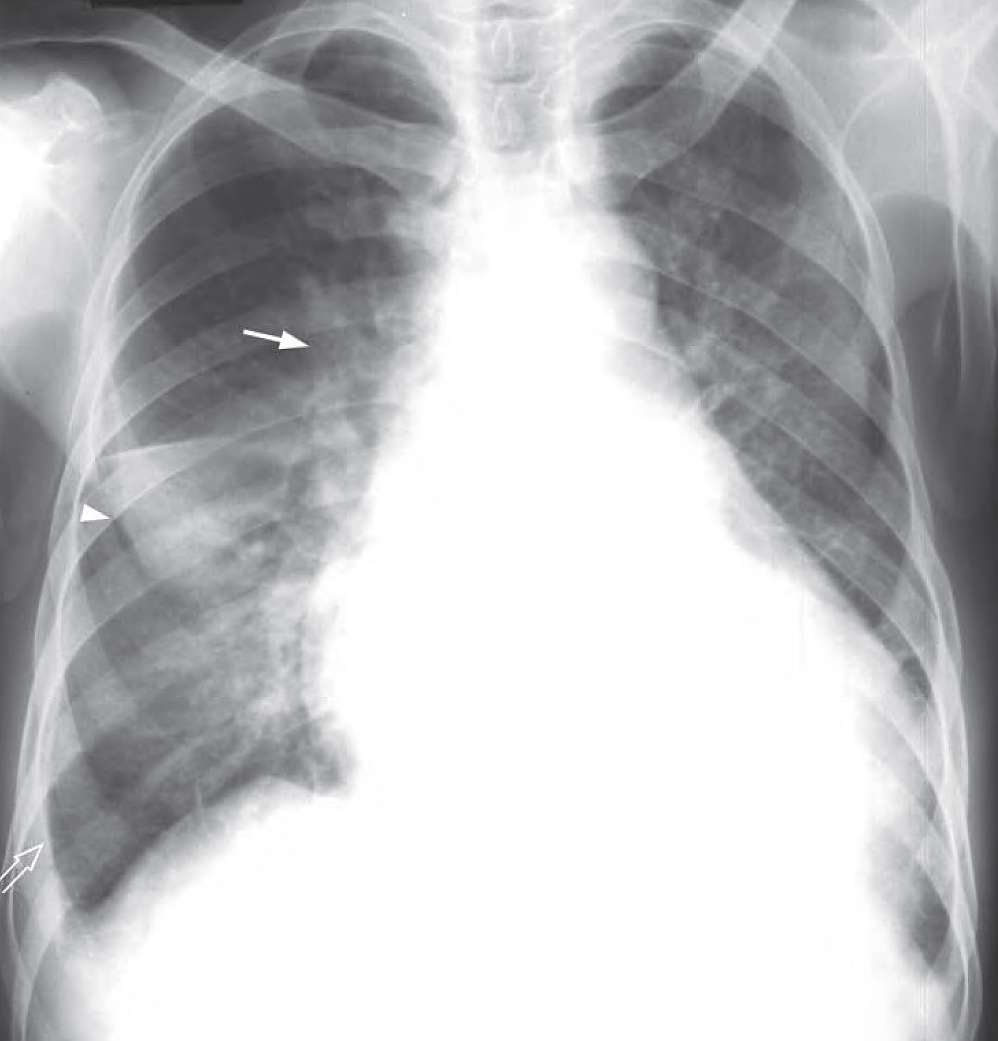

- Cardiomegaly

- Upper lobe venous diversion

- Septal lines (Kerley B lines) best seen in the right lower zone

- Sharply outlined haziness in the right upper zone with no evidence of an air bronchogram suggestive of fluid in the right horizontal fissure

Congestive cardiac failure. Chest radiograph showing cardiomegaly, upper lobe venous diversion (arrow), septal lines (Kerley B lines) best seen in the right lower zone (open arrow) and thickening/fluid in the horizontal fissure (arrowhead). The fluid in the right horizontal fissure is sometimes called the ‘Phantom tumour’ as it may disappear on subsequent radiographs as the patient’s condition improves